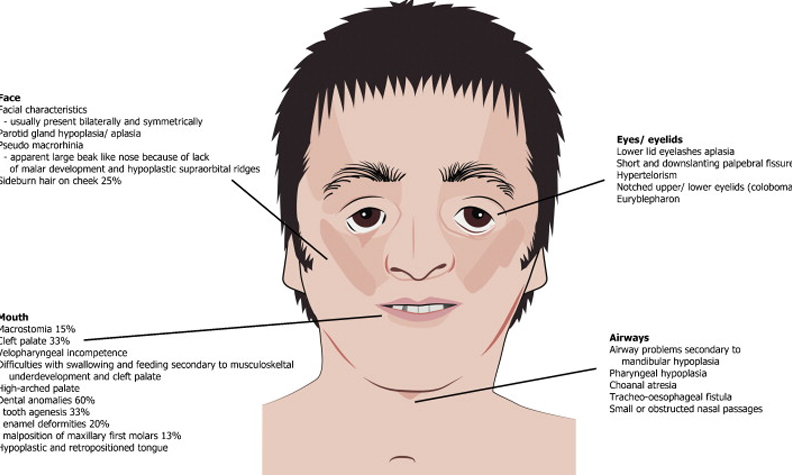

Depicting Derm Difference: "Wonder"

Middle School. Hormonal changes & physical growth combine with the social transition from child to quasi-adult. Does anyone get through it unscathed? While trying to fit in, any small flaw becomes magnified. Imagine the challenge if one was entering that setting with a birth defect syndrome. The film "Wonder," based on the YA novel, captures that period. After being homeschooled by mom Julia Roberts, fictional fellow Auggie (Jacob Tremblay) is brought for his first day of class.

Auggie was born with mandibulofacial dysostosis, also called Treacher Collins syndrome or TCS. In this rare condition, bones and facial tissues develop abnormally.

This illustration shows some of the variety of defects that can occur in TCS. The nose can appear beak-like and the eyelids can droop. The jaw may be abnormal, some develop a cleft palate.

The bony defects can result in not just cosmetic, but also functional issues. The inner ear can be affected, which is true in Auggies case. Spoiler Ear-lert: He eventually needs hearing aids. There can be vision and breathing problems.

Typically, intelligence is normal. Despite the challenges, affected people move forward with their lives. Jono Lancaster was born with TCS and was abandoned by his birth parents. He was adopted and grew to become an inspirational speaker with a long-time girlfriend.

Actor Jacob Tremblay does not have TCS, but underwent hours of prosthetic makeup to recreate the look of the condition. There is no cure for TCS. Various surgeries are performed to restore appearance and function.

Props to "Wonder" for presenting TCS as a challenging but survivable condition. Any movie that shows skin issues in a positive and sympathetic light is "Wonder"-ful in our eyes.